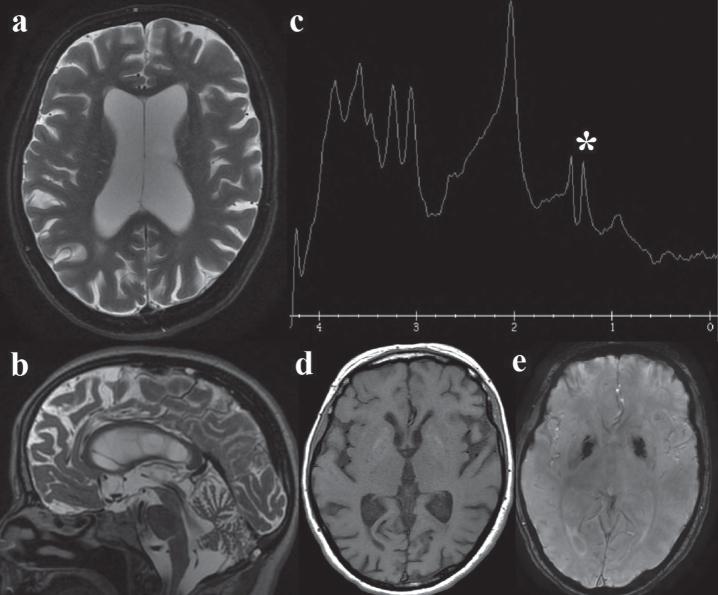

Here we report the case of an Italian 49-years old female presenting with encephalomyopathy, chronic proteinuric kidney disease and a new heteroplasmic m.3274_3275delAC MT-TL1 gene mutation.

本文报告了一例意大利 49 岁女性,表现为脑病、慢性蛋白尿性肾病和新的异质性 m.3274_3275delAC MT-TL1 基因突变。